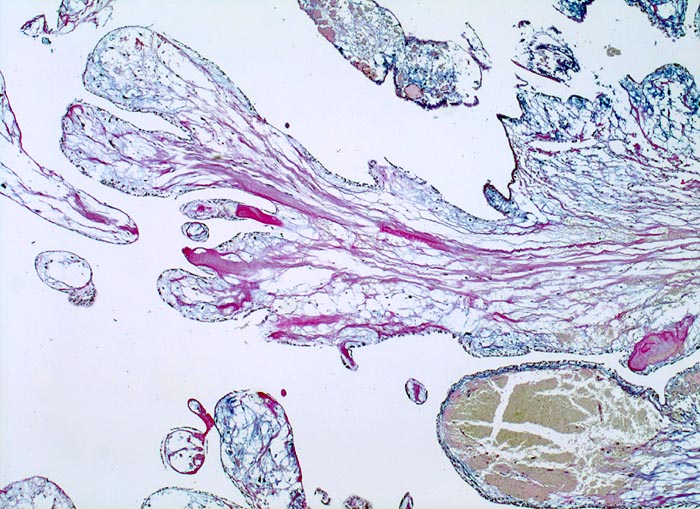

Vorhofmyxom

benigner Tumor

Herz Vorhof

Papillär gebauter Tumor mit ödematösem myxoidem Stroma. Fokale Stromablutungen.

Histologie

25